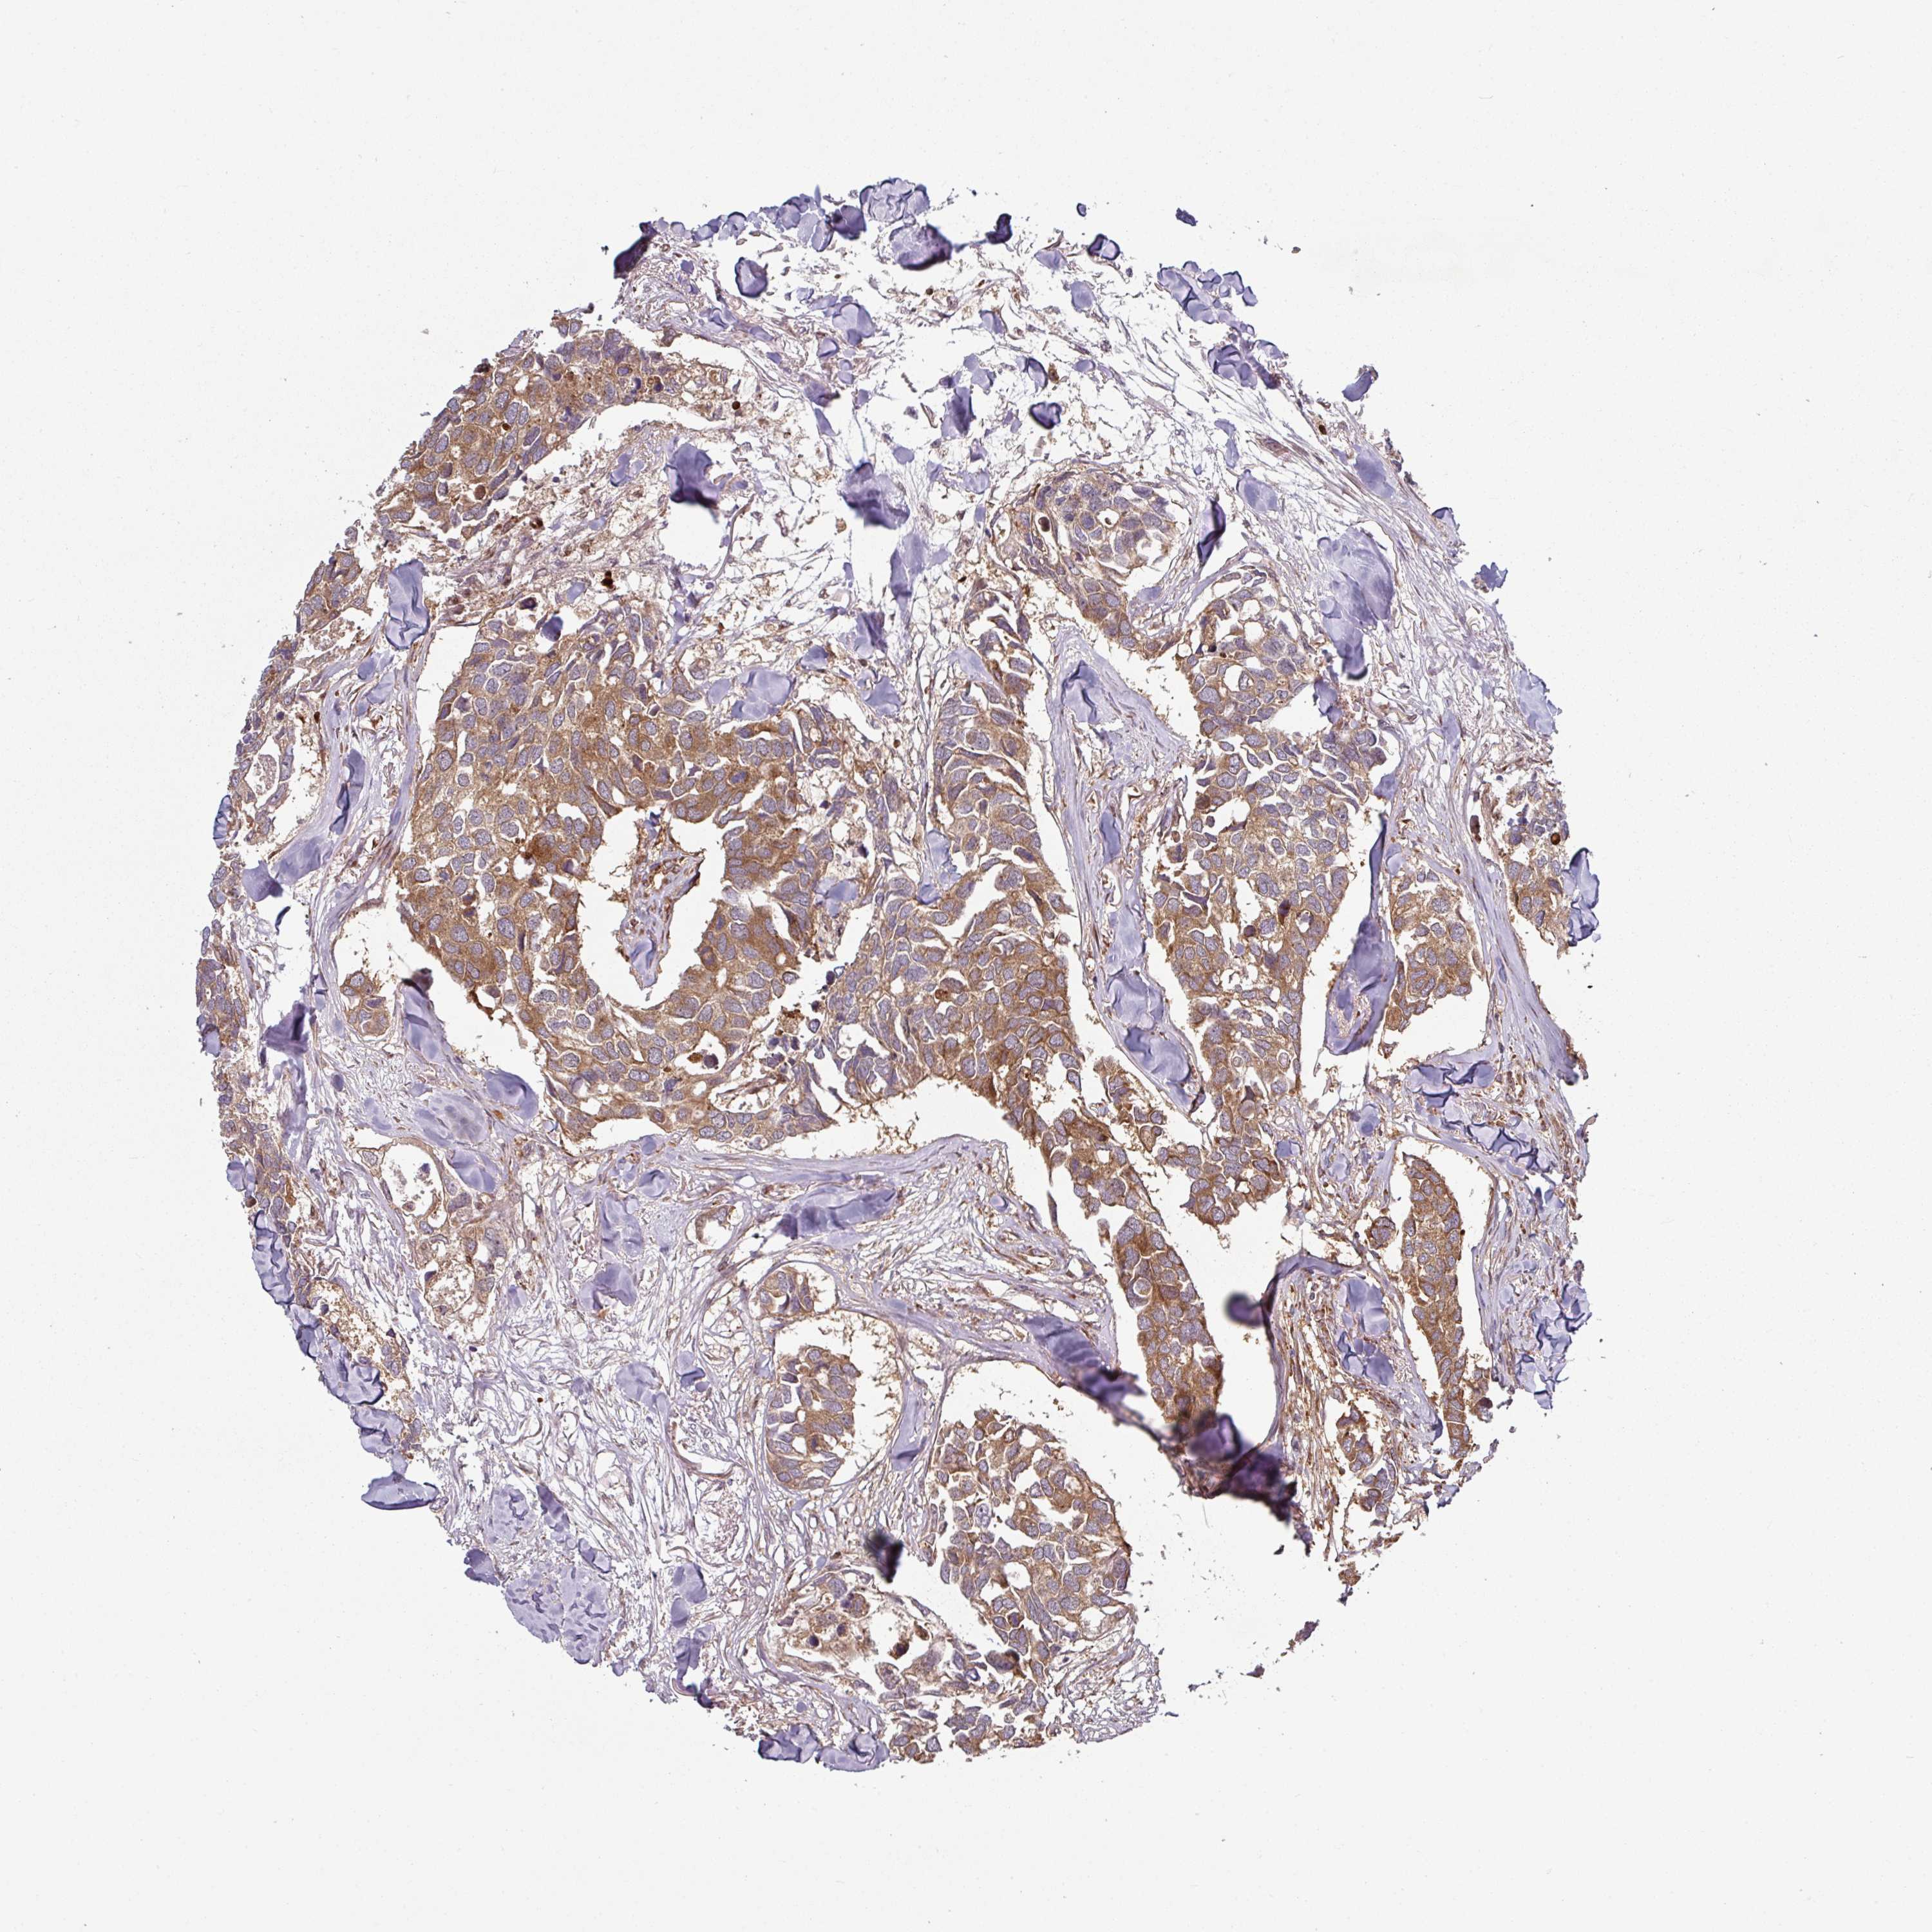

CANCER BREAST CANCER Show tissue menu

BRCA TCGA BRCA VALIDATION PROTEIN EXPRESSION